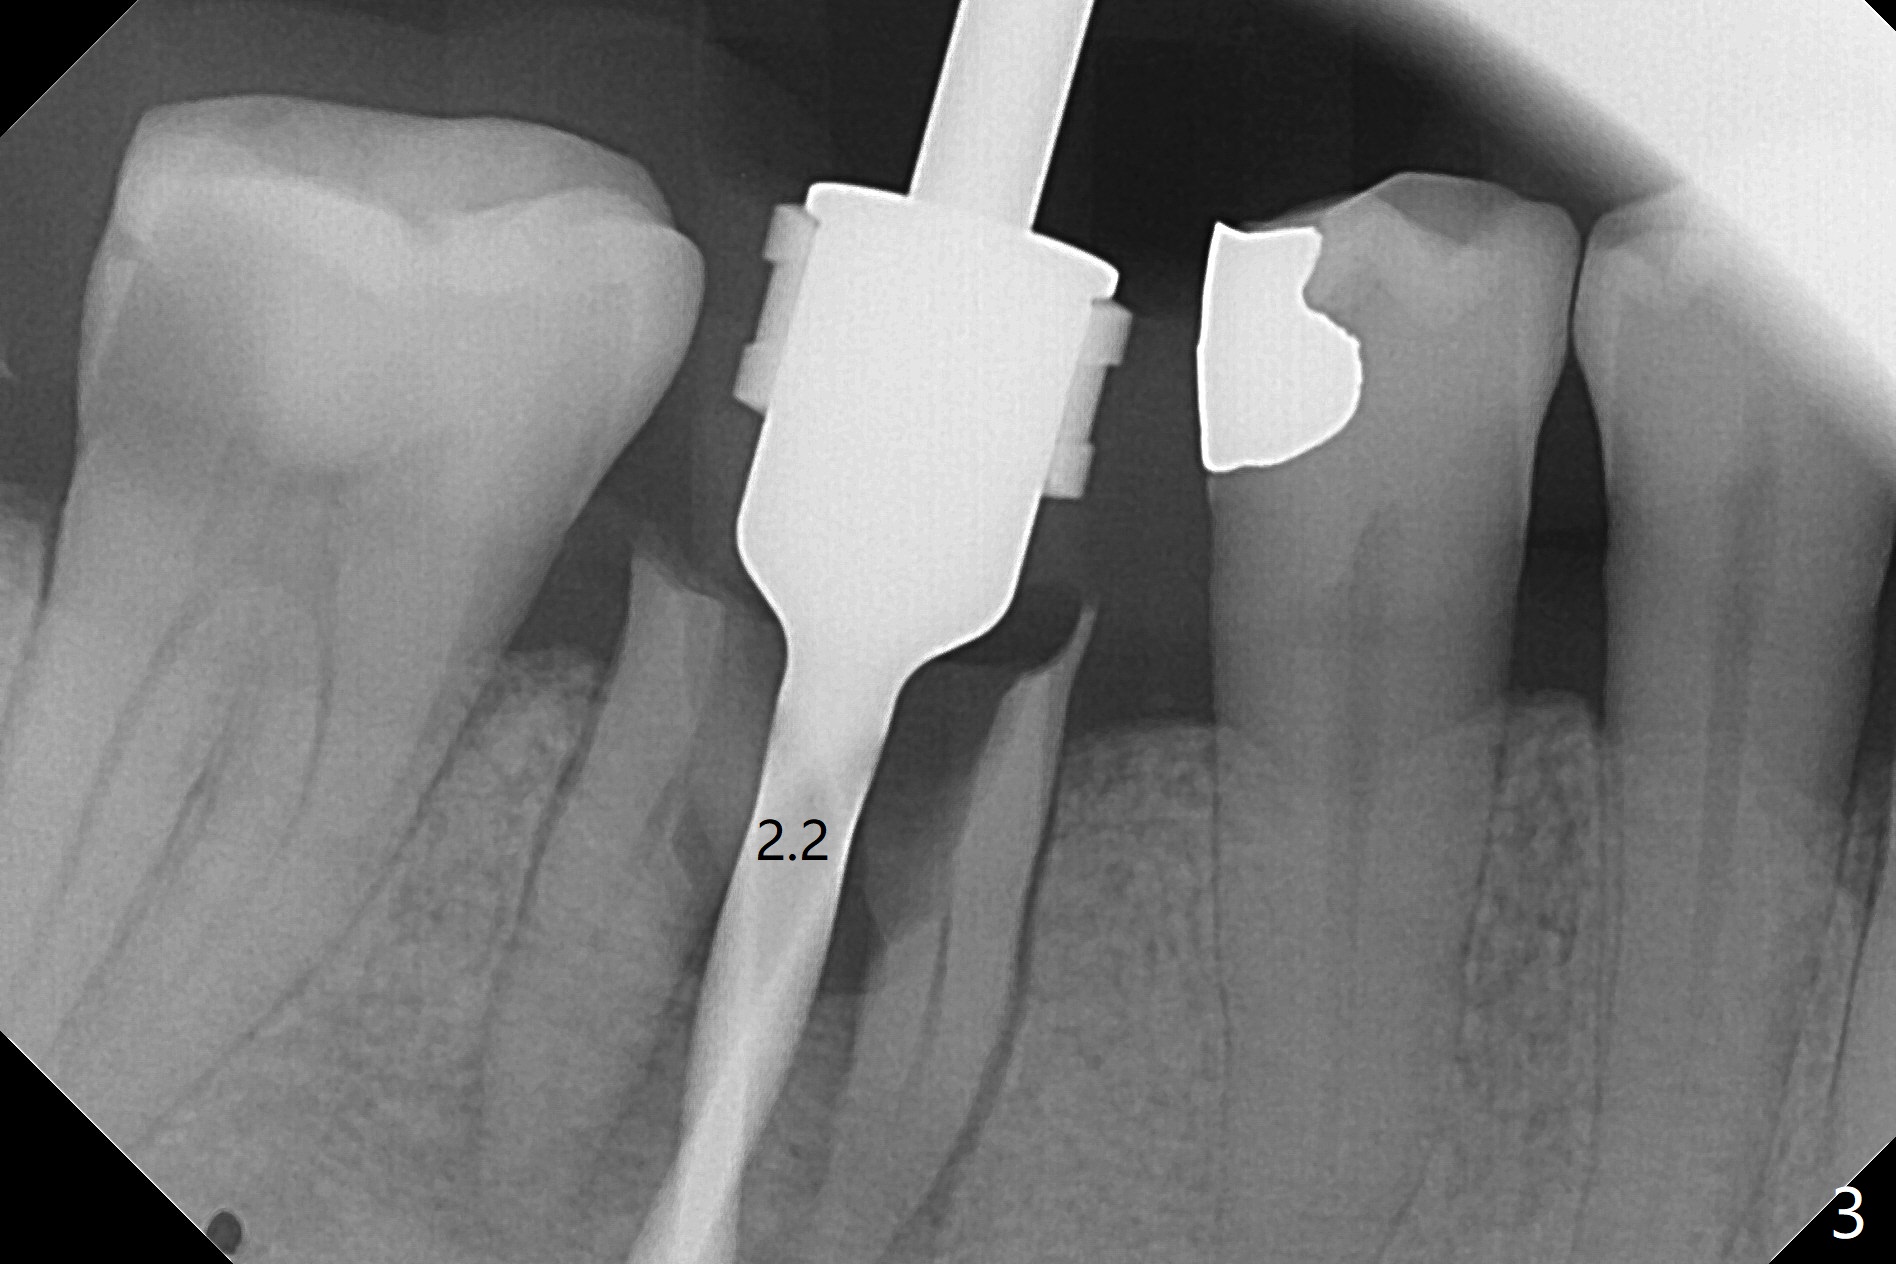

As planned, the crown of the tooth #30 with lingual (Fig.1 L) caries is removed and flattened with surgical handpiece so that the guide is able to be seated without interference. The osteotomy by 10.5 mm offset bone trimmer is lingual (Fig.2 white circle; due to in part the lingual caries and in part design error); in order to let the osteotomy to bounce back buccal, the part of the buccal roots are removed by surgical bur (arrows). The initial osteotomy by 2.2 mm drill is in the middle of the septum (Fig.3). After the last drill (3.5x11.5), the remaining roots are easily removed with proximators; a 4x11 mm dummy implant is placed with low stability and supracrestal lingual (Fig.4). Therefore a 4.5x9 mm final implant is placed with low torque. Following 4x11.5 mm drill, the torque increases to 20 Ncm. With insertion of healing screw, sticky bone (Fig.4 *: .5-1 mm cortical/cancellous allograft) is heavily packed around the implant (arrow), which apparently allows removal of the healing screw and placement of a 6x5.7(3) mm pair abutment without loosening the underlying implant. More bone graft is placed (Fig.6), followed by 2 pieces of PRF membranes. Although the implant is slightly buccally placed (Fig.7, due to over-removal of the buccal root, Fig.2 arrows), it is placed in the septum (Fig.8 S). To further compensate for the low implant stability, setting acrylic is applied in the edentulous area, particularly into the undercuts of the neighboring teeth (Fig.9 *) and around the abutment. The lingual margin of the acrylic dressing is extended (Fig.10 arrow) to cover the soft tissue defect associated with the lingual caries. As compared to the design (4x10 mm, Fig.11), the implant (4.5x9 mm, Fig.12) is placed buccal and ~ 2 mm deeper, reducing the chance of periimplantitis. The acrylic dressing is in place, but has mobility. The gingiva is healthy 2 weeks postop. The dressing is removed 1 month postop; the socket heals around the abutment buccal (Fig.13) and lingual (Fig.14). In spite of the immediate provisional, the abutment margin is substantially subgingival mesial 4 months postop, extremely difficult to take impression. A smaller diameter and longer cuff abutment is placed (Fig.15). The lingual gingiva heals normal 5 months postop, immediately before cementation (Fig.16).